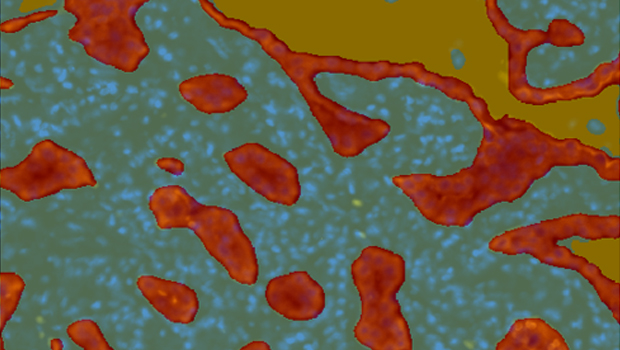

根据肿瘤蛋白标记或组织形态将组织划分为肿瘤实质区和间质区,并统计组织区域面积、阳性细胞数量、百分比、密度。

空间浸润分析用于分析病灶区域(如肿瘤、坏死、纤维化等)周围某类细胞的浸润情况。如常用于肿瘤免疫浸润分析。